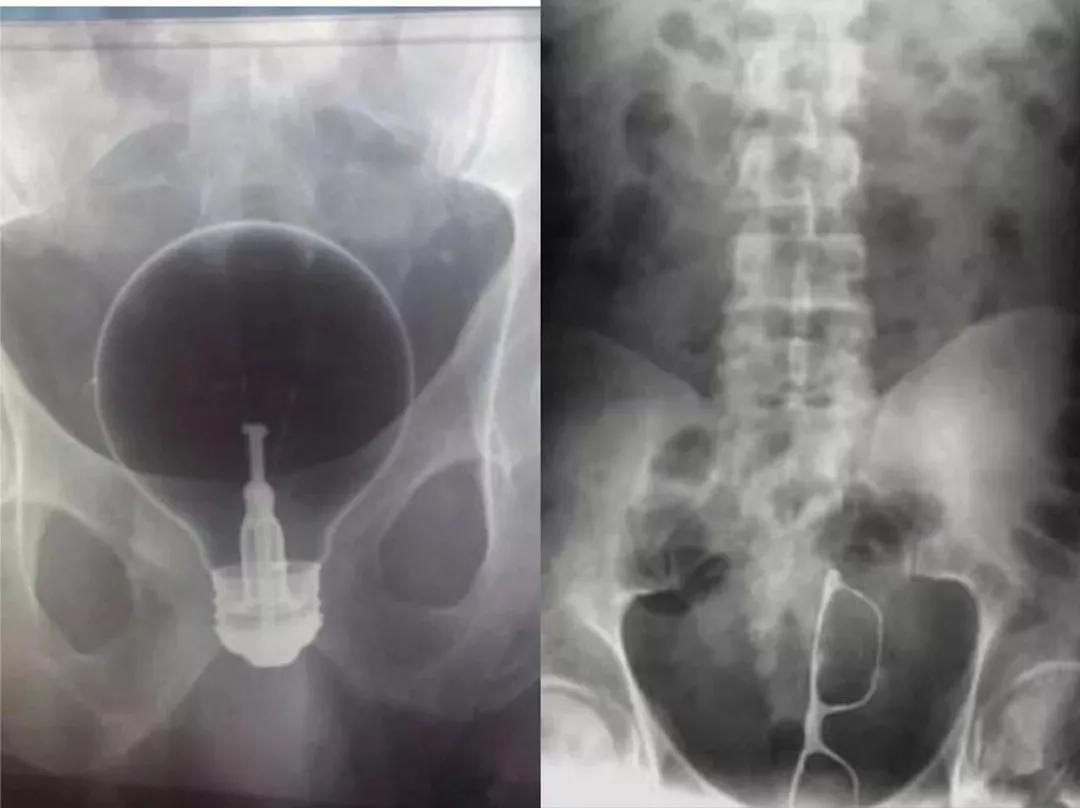

看着这灯泡和眼镜.......

不仅浑身散发出正道的光

下半身还散发着炽热且智慧的光??

偶尔也会出现沉默的磁带和落寞的插头

据某网站统计,以下是在男性*体下**内发现的奇葩物体的排行榜:

1、小螺丝

2、尖锐的玩具

3、金属性玩具

4、塑料勺子

5、多米诺骨牌

6、塑料香波瓶

7、回形针

8、电线